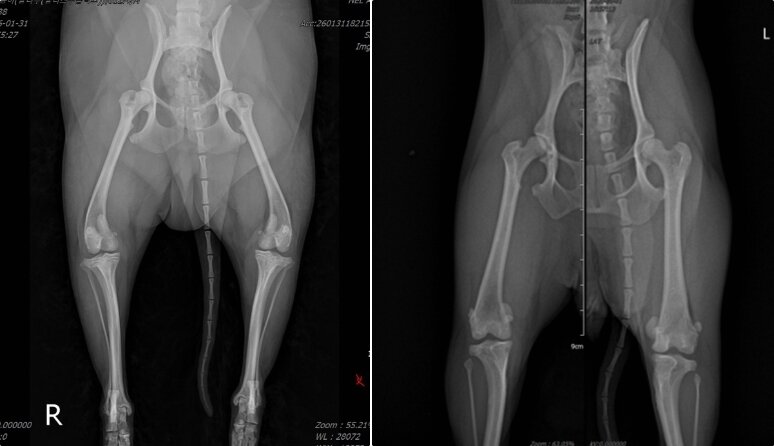

왼쪽처럼 촬영 시 무릎뼈(슬개골)와 허벅지뼈가 안쪽으로 돌아가 각도 측정이 어렵다. 오른쪽 사진처럼 허벅지뼈 정렬을 맞춰 촬영해야 변형 정도와 수술 위치를 정밀하게 확인할 수 있다(바르고바르개 제공). ⓒ 뉴스1